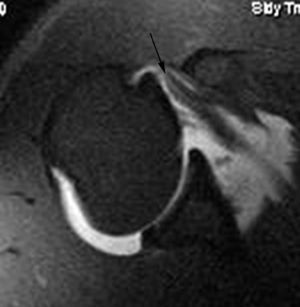

Lesión de Perthes

La lesión de Perthes es similar a la de Bankart, con la excepción de que no existe rotura capsuloperióstica, aunque el periostio puede estar separado del borde anterior del margen glenoideo (fig. 10). Esta lesión puede ser difícil de visualizar, incluso con artrorresonancia, a menos que se obtengan imágenes con la posición de abducción y rotación externa (ABER). En un estudio de 10 casos, verificados quirúrgicamente, Wisher et al17 comprobaron que el 50% de las lesiones de Perthes sólo podían visualizarse en la posición de ABER.

Fig. 10.--Lesión de Perthes. Artrorresonancia T1 con saturación grasa en posición ABER (abducción y rotación externa), donde se observa un arrancamiento parcial del labio glenoideo (flecha) con conservación de la unión capsuloperióstica.